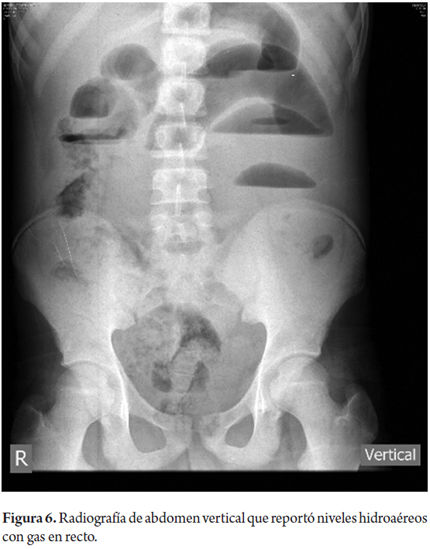

Rx. Abdomen S/CAsas dilatadas >3 cmNiveles hidroaéreosDetención del contraste